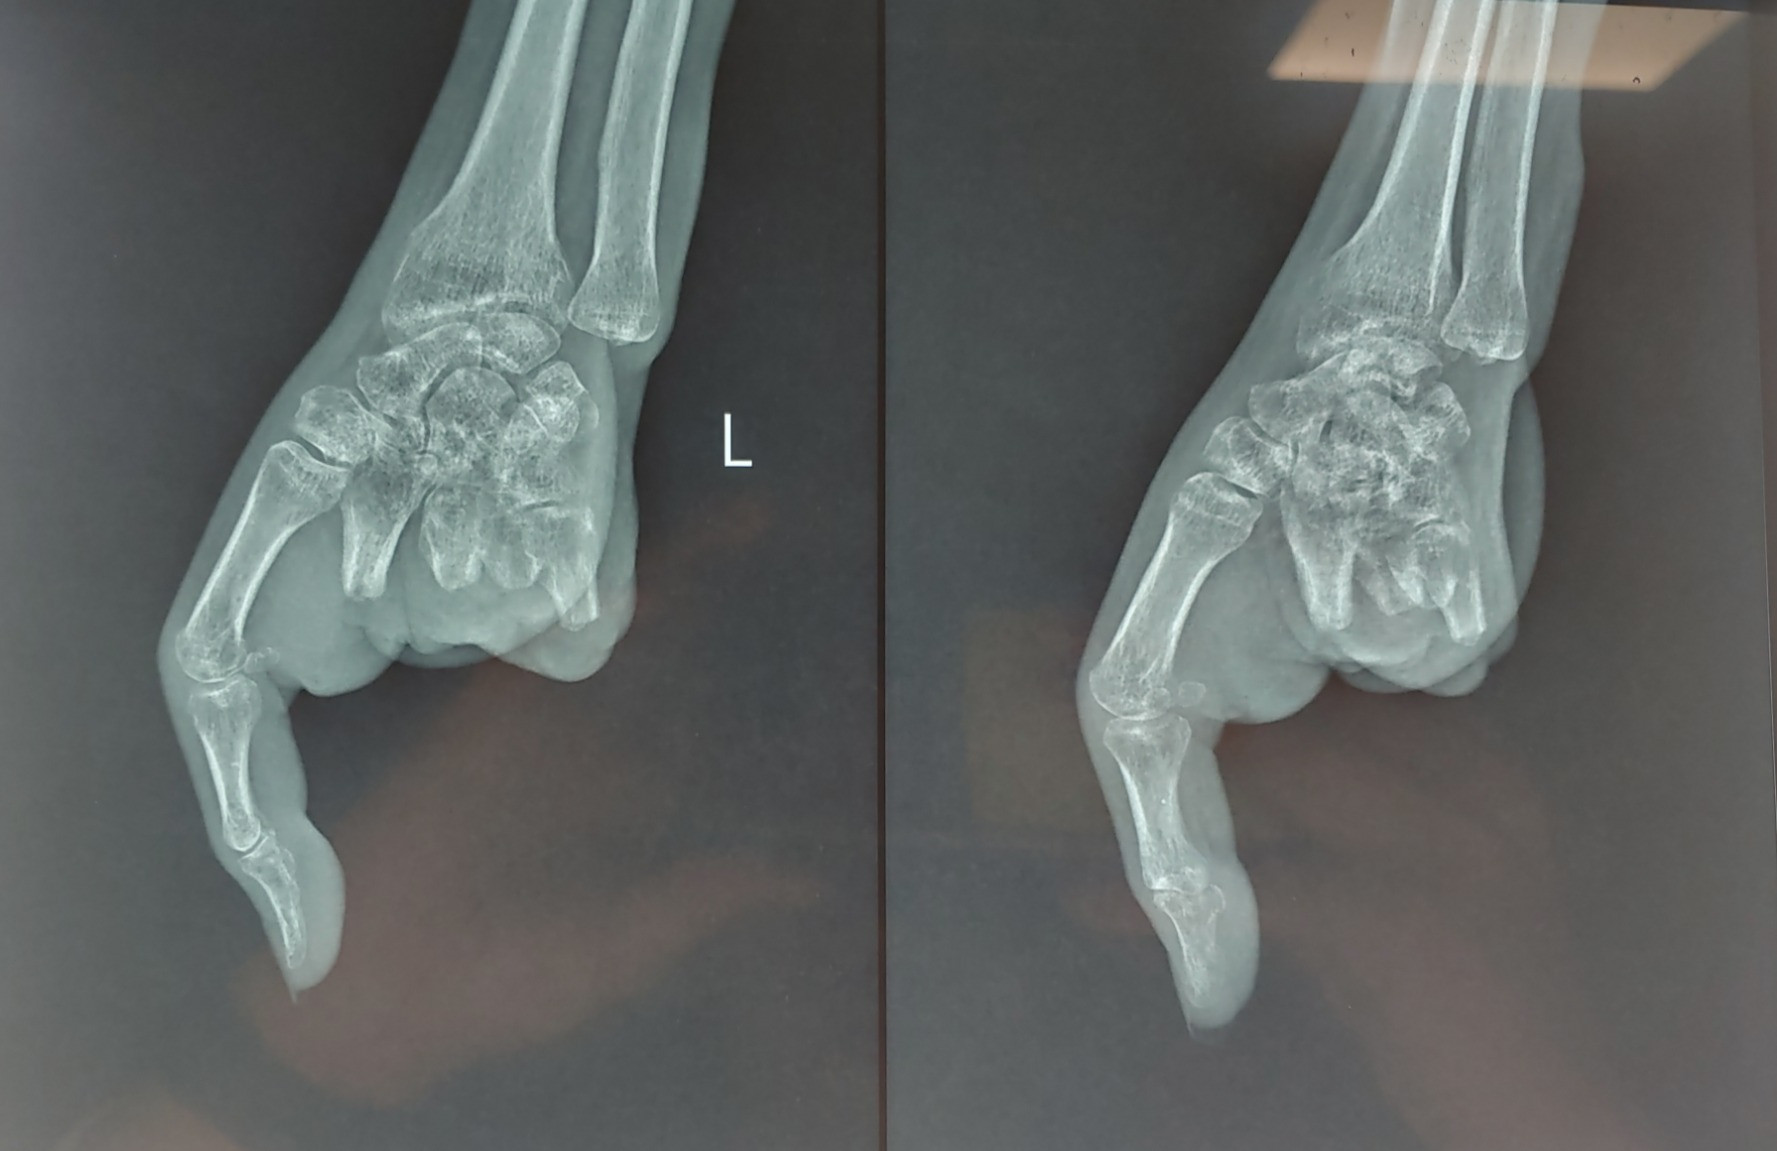

Theo Bệnh viện Quân y 175 (TP.HCM), 3 tháng trước, chị N.T.V (42 tuổi) bị máy xay thịt cuốn bàn tay trái. Tai nạn khiến chị dập nát 4 ngón tay, tổn thương phức tạp. Bệnh nhân được xử lý cấp cứu và chuyển lên phòng phẫu thuật.

Bác sĩ nhận định, 4 ngón tay dập nát, không thể phục hồi, chỉ duy nhất còn ngón tay cái. Do đó, bệnh nhân được phẫu thuật tạo mỏm cụt từ ngón 2 đến ngón 5. Việc mất đi các ngón tay khiến sinh hoạt của chị V. rất khó khăn.

Ba tháng sau tai nạn, phần mềm ổn định, không có dấu hiệu nhiễm trùng, bệnh lý nền được kiểm soát tốt. Các bác sĩ đã tiến hành ghép ngón chân thứ 2, 3 của bàn chân trái đưa lên ngón tay 4, 5 của bàn tay trái, tạo cung cầm nắm cho bệnh nhân.

Bác sĩ chuyên khoa 1 Võ Thành Nhơn, Khoa Phẫu thuật chi trên, Bệnh viện Quân y 175 cho biết, ca phẫu thuật này kéo dài 6 giờ. Ê-kíp đã đưa ra hướng kết hợp xương từ ngón chân lên bàn tay, khâu nối mạch máu, dây thần kinh, gân cơ, phục hồi sự sống của ngón tái tạo.